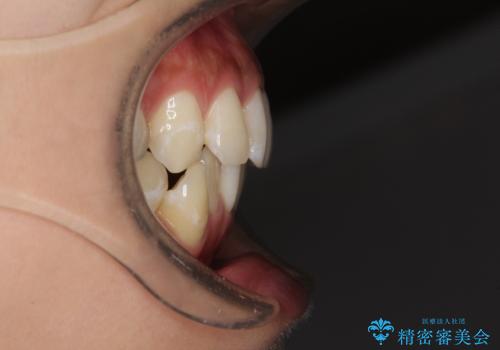

八重歯の再矯正 インビザラインでストレスなく矯正治療

- 学生の頃に矯正治療を行ったものの、保定を怠けてしまったことによる後戻りを気にして来院された患者様です。

下顎の八重歯が上顎歯列に収まる過程で咬みにくさがありましたが、最終的には、咬み合わせも安定し、きれいに歯列を整えることができました。